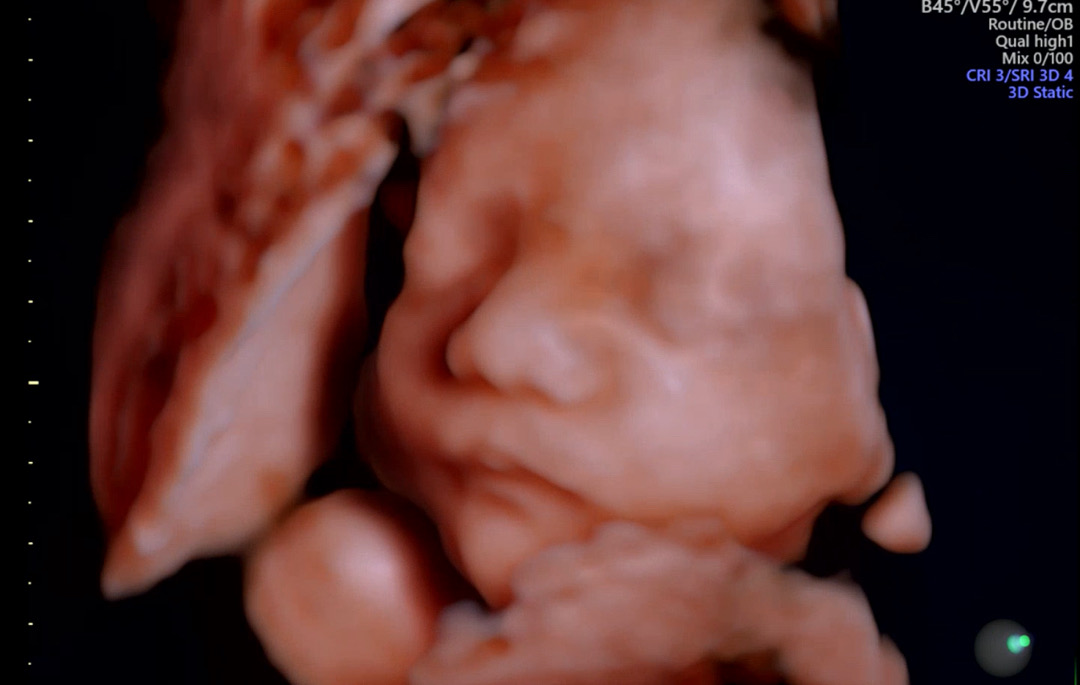

찰떡이 초음파❤️

저두 초음파 보구왔습니다 :) 벌써 30주차 되었네요..🥹 주수가 지날수록 두려움에 앞서지만 그래도 잘 해낼수 있겠죠? 초산이라 걱정이 많은 예비맘입니다 날씨 추워지는데 엄마들 감기조심하세용